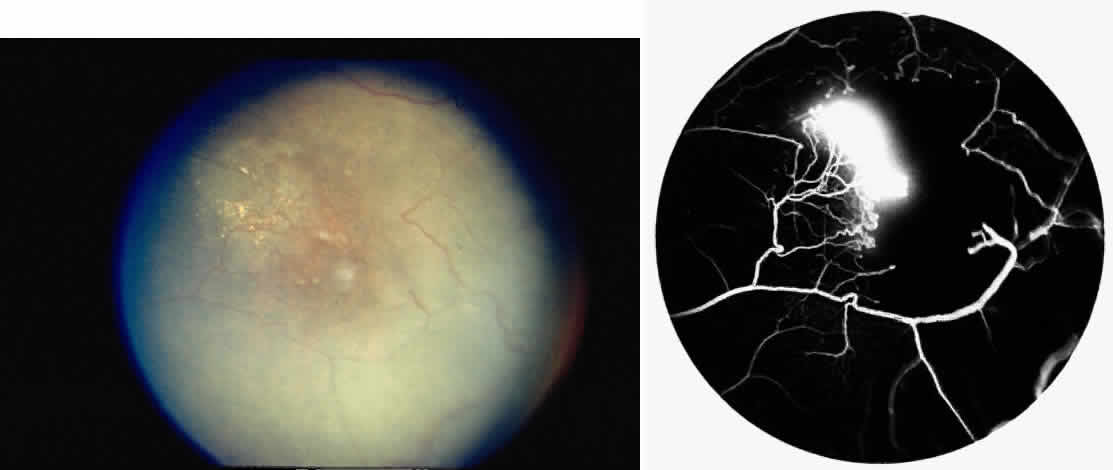

Epiretinal membranes may produce visual loss in patients with sickle cell disease. Macular epiretinal membranes are seen more frequently in eyes with retinal neovascularization, retinal tears, and vitreous hemorrhage, as well as in eyes that have had laser treatment or surgery of the retina or vitreous.78 Progressive visual loss from macular distortion has been reported in up to 32% of these patients over a 2.5-year period.79 Peripheral neovascularization may stimulate formation of epiretinal membranes by transudation of plasma and erythrocytes into the vitreous, disrupting the vitreous cortex and inducing posterior vitreous detachment. Successful treatment of the neovascular tissue reduces the risk of epiretinal membrane development by approximately 30%.79 Although spontaneous separation of epiretinal membranes following treatment of peripheral neovascularization has been observed, surgical removal may be considered when patients exhibit moderate to severe visual loss (Fig. 6).80,81

Fig. 6. A. Preoperative photograph of the left eye of a 64-year-old woman with SC disease, who received cryotherapy and scatter photocoagulation therapy for proliferative sickle retinopathy, resulting in the development of an epiretinal membrane. At this point, visual acuity was 20/400. B. Postoperative photograph after vitrectomy and removal of the epiretinal membrane. Visual acuity was improved to 20/60. This patient received preoperative exchange transfusions and postoperative oxygen therapy.